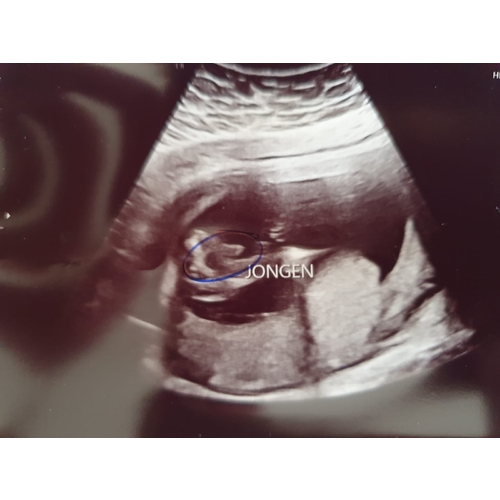

Ik krijg ook een jongetje 💙 Dit is mijn echo 🥰

Een jongetje 💙

Met 14 weken!